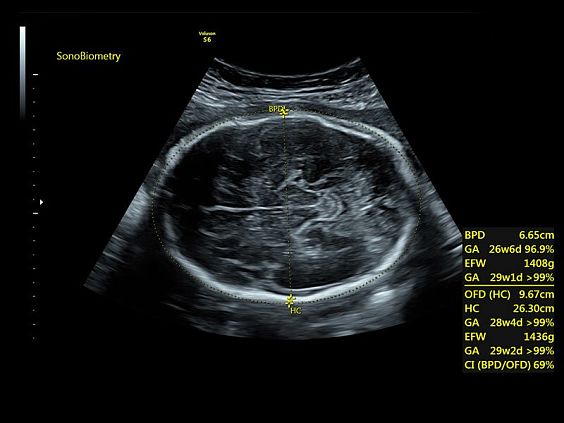

Клинические изображения

- SonoBiometry (автоматическое измерение BPD, AC, HC, HL, FL)

- SonoBiometry (автоматическое измерение BPD, AC, HC, HL, FL)

- Технология автоматической фетометрии в 2D режиме — SonoBiometry для определения бипариетального размера, окружности головы, окружности живота, длины бедра и плеча плода.